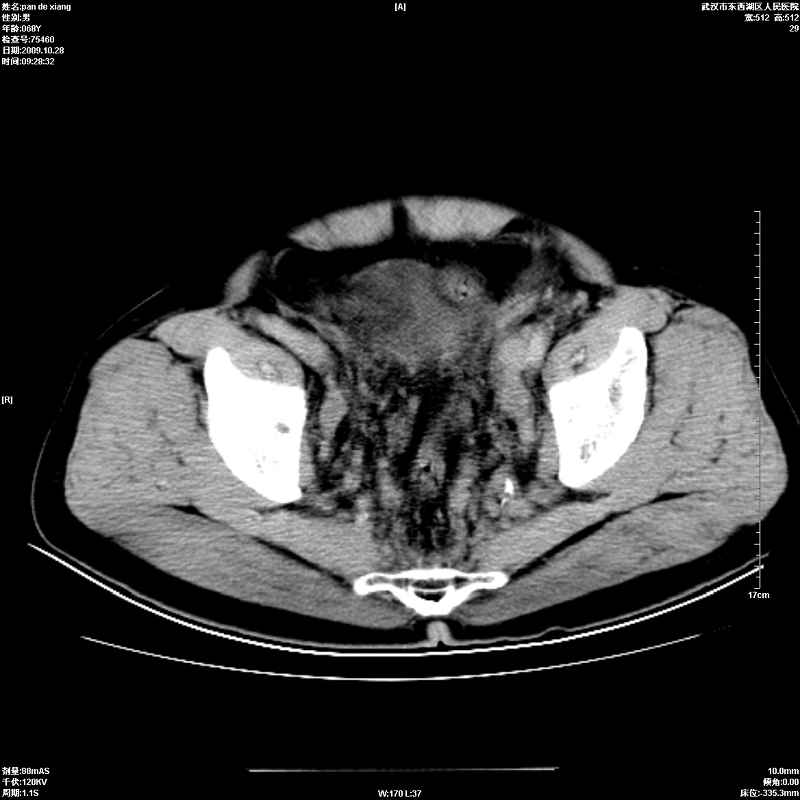

以下是引用杀毒软件在2009-10-28 20:41:00的发言:[br]结合临床考虑---白血病双肾改变或淋巴瘤。

以下是引用zxl51642在2009-10-29 9:59:00的发言:[br]结合临床“单克隆免疫球蛋白血症”,考虑双肾为继发损害并肾功能不全(尿中大量igg及少量iga、igm等大分子免疫球蛋白滤出所致继发损害),椎前软组织肿块为髓外造血。与浆细胞瘤有区别,平扫时有战友说的很清楚。